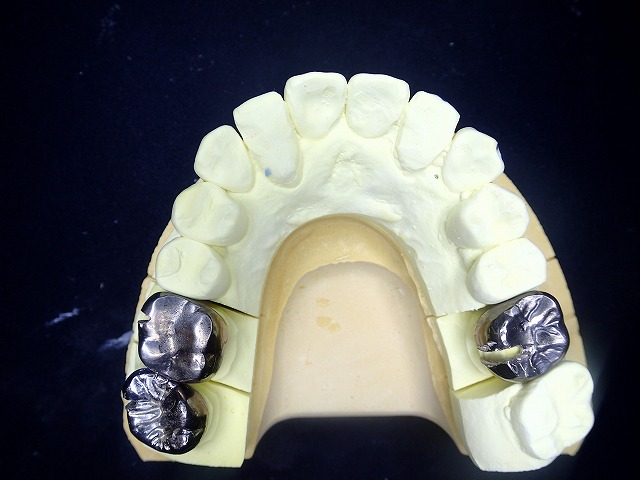

前歯の治療後 奥歯の銀歯を白くしたいとご希望

金属クラウンとジルコニアクラウンの比較

その後 銀歯も白くしたいとのご希望がありました

ジルコニアとの比較すると

両側の奥歯を銀歯からジルコニアに交換